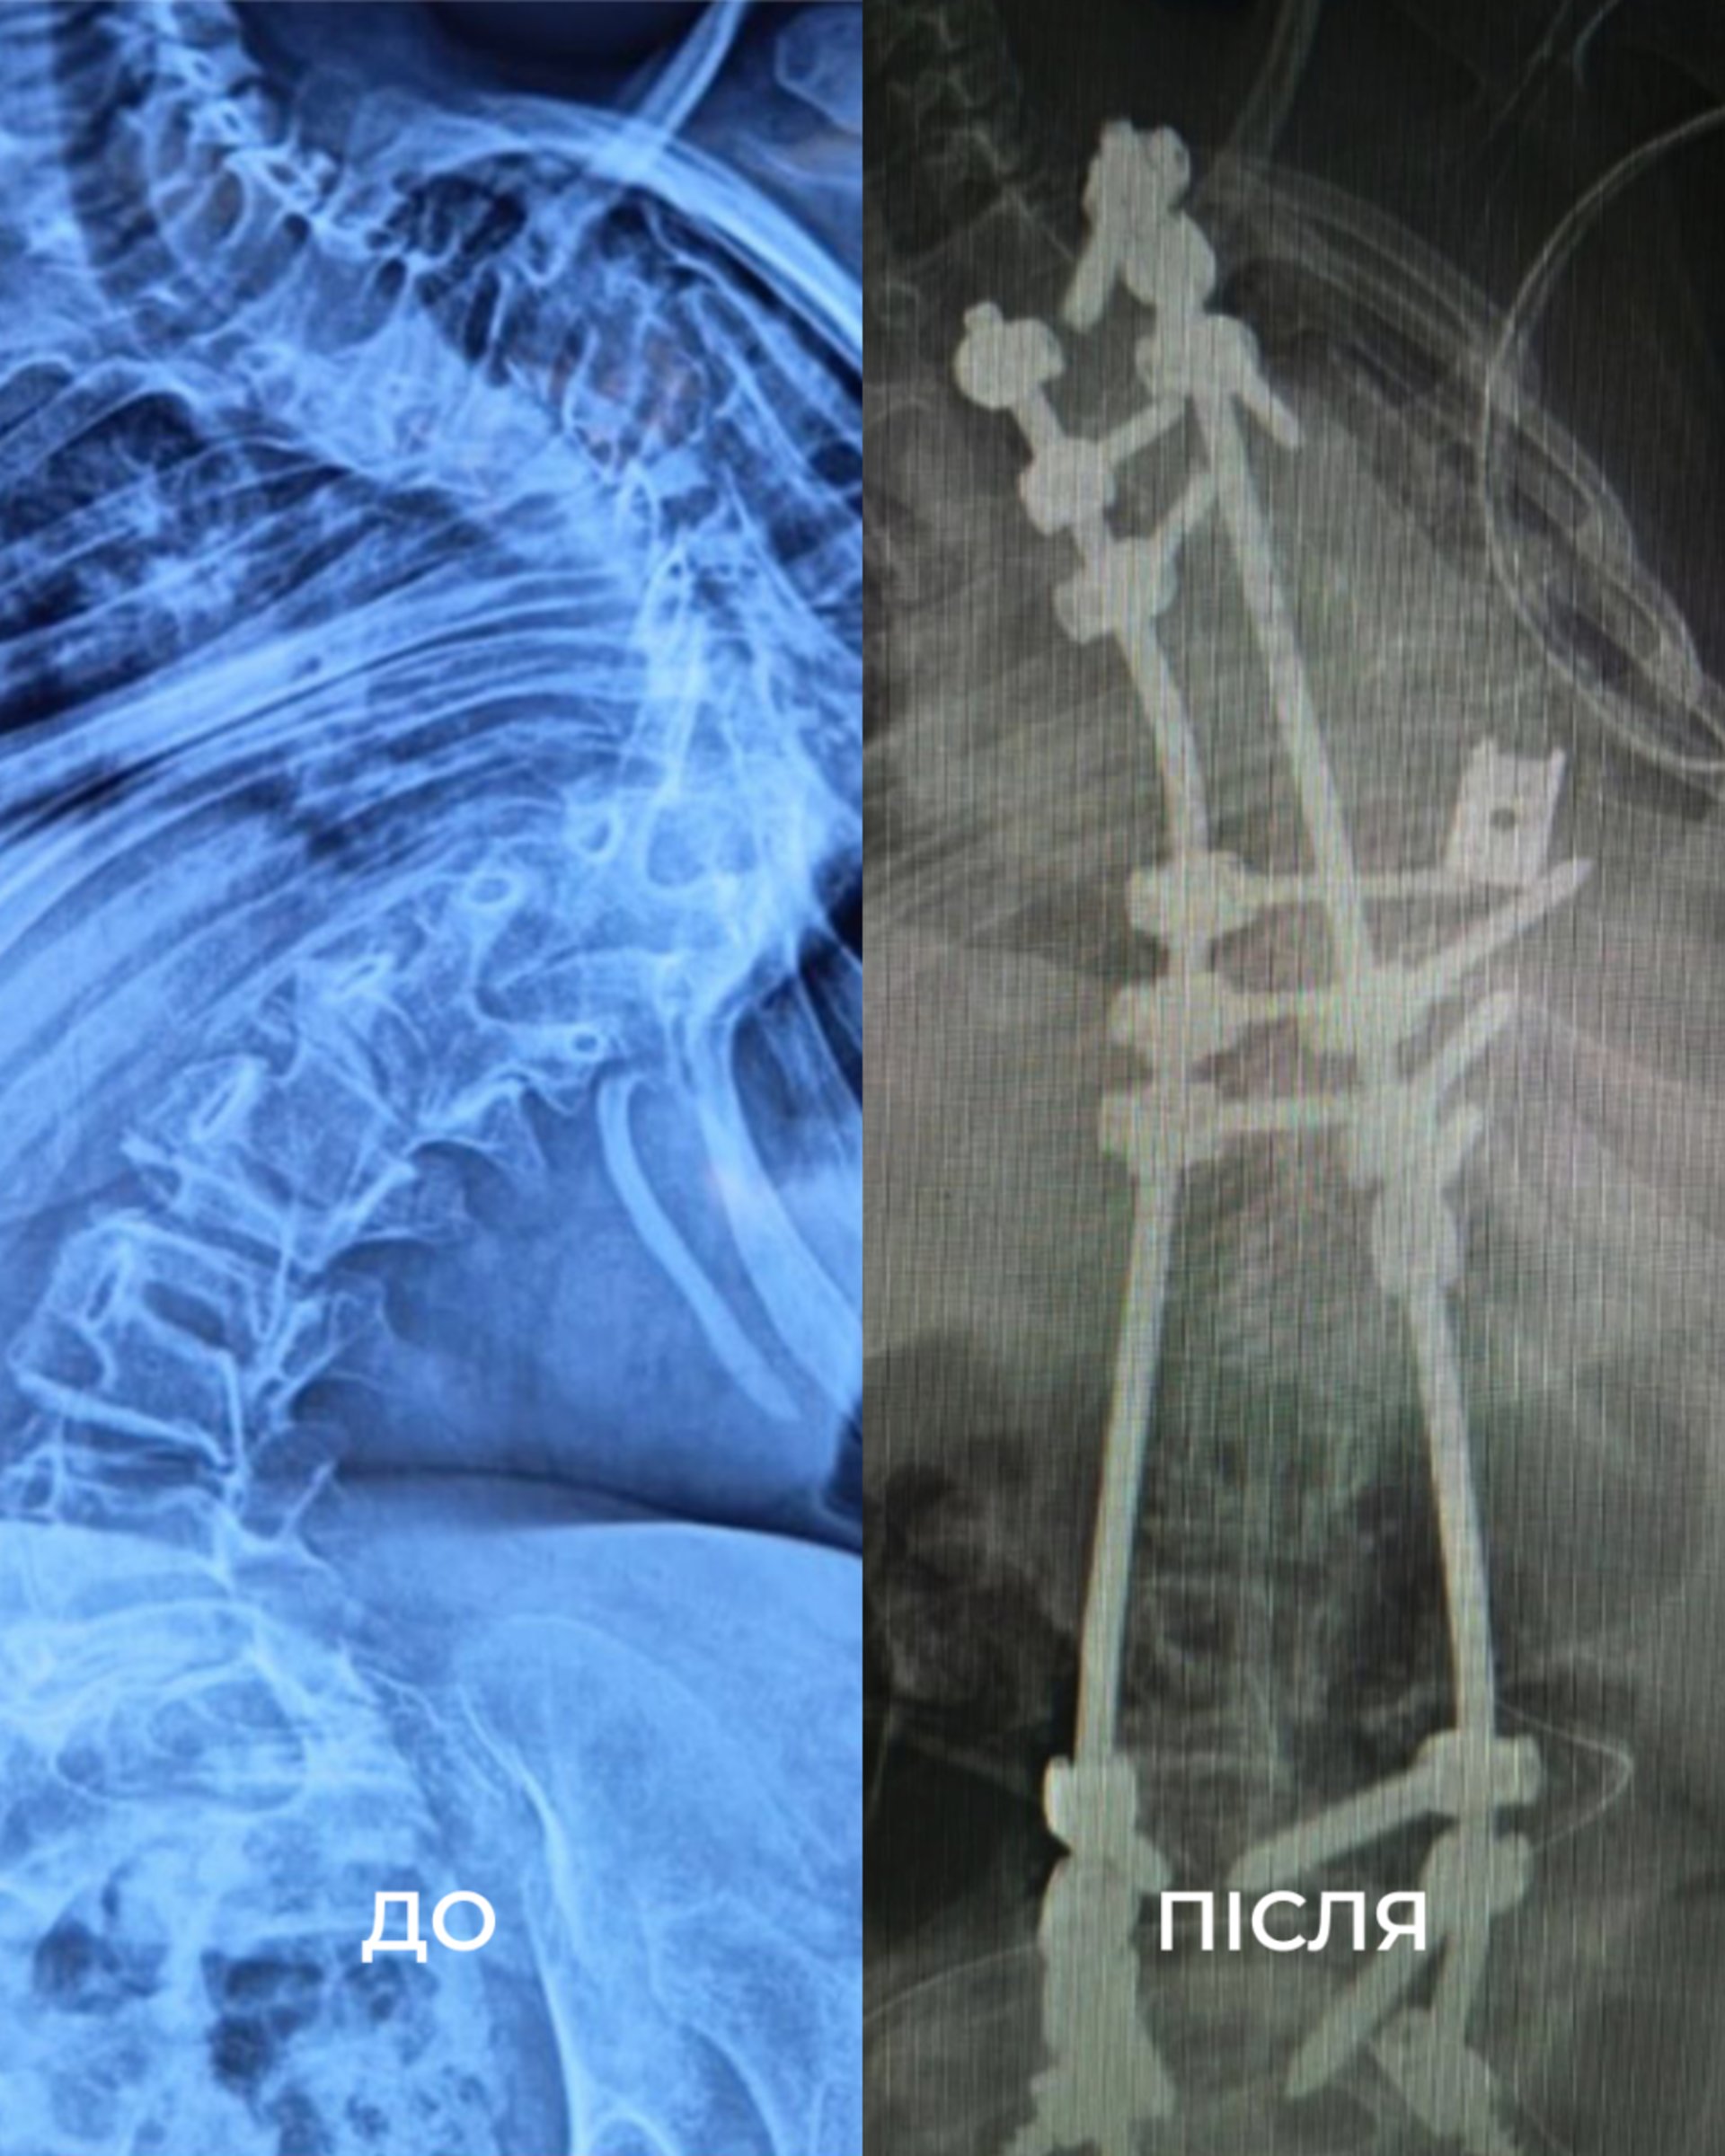

У Львові хірургам вдалося вирівняти хребет дівчинки на 85 відсотків (ФОТО)

У Львові прооперували дитину зі сколіозом найвищого ступеня.

З роками стан лише погіршувався: невпинний біль, задишка, неможливість довго сидіти. Хребет дитини викривився аж на 160 градусів. Вдома дівчинка пересувалася з ходунцями, у школі – на кріслі колісному. Часто бувала в лікарнях та на реабілітації.

«Щоб виправити її сколіоз, нам потрібно було видалити цілий хребець. У перший день операції ми закріпили її хребет гвинтами. А вже на другий день – видалили кілька ребер, ізолювали спинний мозок та встановили титанову клітку для підтримки хребта. А потім повільно виправляли її разом з моєю колегою, нейрофізіологинею Меган Маллані», - розповідає американський ортопед-травматолог Марк Диржка. Після двох операцій, 18 годин наркозу та через надто слабкі м’язи, два наступні тижні Віка пробула в реанімації під киснем. Але результат того вартував – хірургам вдалося вирівняти хребет дівчинки на 85%.

Ось що каже мама Віки: «Спина дійсно змінилася. Немає більше того горбу з ребер. Вона витягнулася, стала вища. Ми здивовані! І лікарі самі сказали, що зробили більше, ніж очікували».